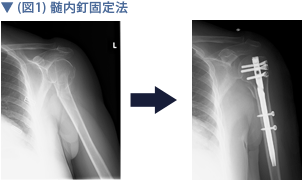

上腕骨近位端骨折について こんな時は救急外来へ 症例別q A 社会医療法人 有隣会 東大阪病院 大阪市 城東区

上腕骨近位端骨折 一般社団法人 日本骨折治療学会 骨折の解説

上腕骨近位端骨折その2 愛知県岡崎市 整形外科 リウマチ科 エコーガイド下筋膜リリース ませぎ整形外科

上腕骨近位端骨折におけるneer分類 たくみロドリゲス 運動器理学療法士 Note

骨折日記 今回の手術内容 新しいことを知るのって楽しい